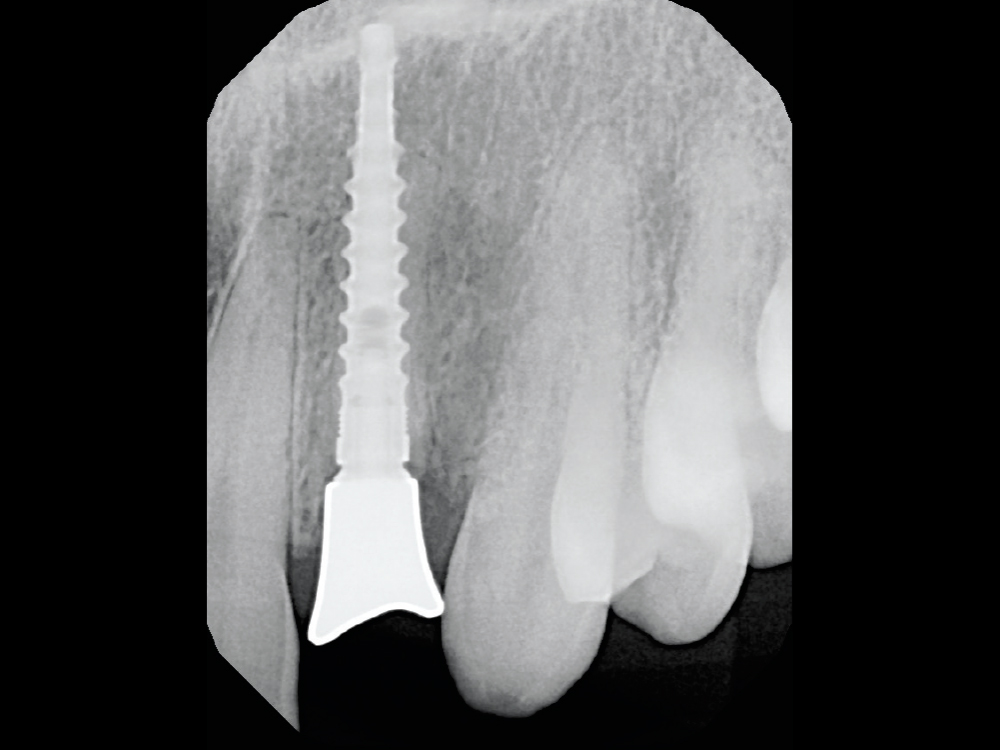

This radiograph shows the Glidewell HT 3.0 implant with the seated custom healing abutment.

Figure 14: This radiograph shows the Glidewell HT 3.0 implant with the seated custom healing abutment.